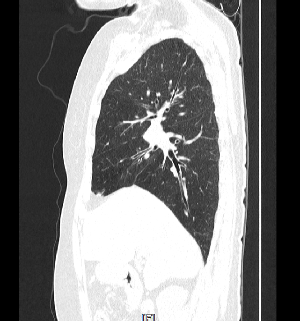

의료용 방사선을 이용하는 X-ray 검사와 비교할 때 인체의 해부학적 구조물이 겹쳐져 보이지 않고 인체의 축상면을 영상으로 획득합니다.

획득된 영상을 전산화된 프로그램을 이용하여 3차원(3D) 영상으로 재구성이 용이하며 인체의 시상면, 관상면 재구성도 가능합니다.